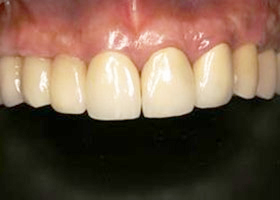

4. 病患最終X光片。

proimages/case/Artificial_implant/all-5.jpg